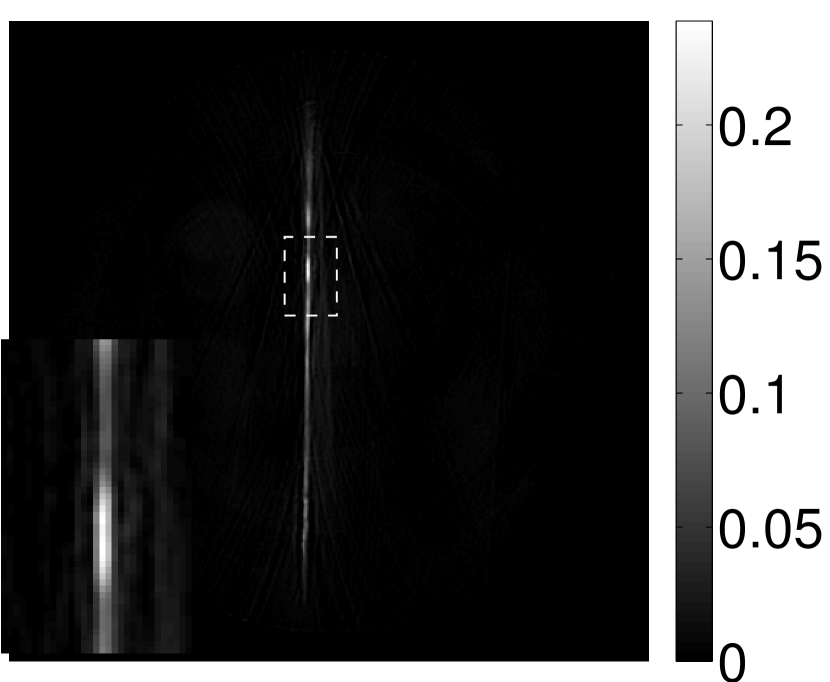

The images and EIRs reconstructed by use of the VP algorithm that was based on the 2D imaging model that neglected the SIR are shown in Figures 15 and 16. The latter figure contains results corresponding to different values for the regularization parameter . From Fig. 15, it can be observed that use of the conventional iterative method that utilized the measured EIR resulted in distortions and loss of details in the reconstructed images. Use of the VP algorithm improved the contrast and the details in the reconstructed images (Fig. 15(c) and 16(a)). Furthermore, the images reconstructed by use of the VP algorithm had a more uniform background.

In Figure 17, the results corresponding to use of the 3D imaging model that incorporated SIR effects are shown. The EIR estimated by the VP algorithm is also shown. In Figure 18, images and EIRs reconstructed by use of the VP algorithm with different regularization parameters values are shown.

Similar to the case described above where the transducer SIR was neglected, these results reveal that use of the VP algorithm can produce images with a cleaner background and enhanced spatial resolution than yielded by use of a conventional iterative algorithm that employed the measured EIR. For example, detailed information regarding the vessels near the organ’s periphery was better preserved by the VP algorithm than by the conventional iterative algorithm. These images corroborate our assertion that the VP algorithm can significantly reduce the artifacts and distortions in the reconstructed image. It is also worth pointing out that, unlike the numerical phantom studies, the artifacts and distortions in the images may be caused not only by the inaccurate EIR but also by other factors, such as neglecting acoustic heterogeneities and the variation of the EIRs among the elements of the transducer array. In such cases, the EIR estimated by the VP algorithm represents an effective system impulse response that minimizes the inconsistency between the measured data and the imaging model.